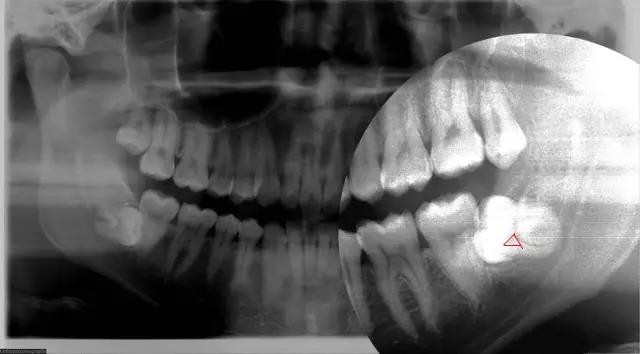

其次,自身的牙齒情況,據醫生專(zhuan) 業(ye) 介紹,目前拔牙可以分為(wei) 前牙,後牙,以及複雜牙等多種不同的牙齒拔除類型,智齒就屬於(yu) 複雜牙拔除這一類,所以價(jia) 格自然要比前牙和後牙拔除和正畸拔牙等要貴一些。